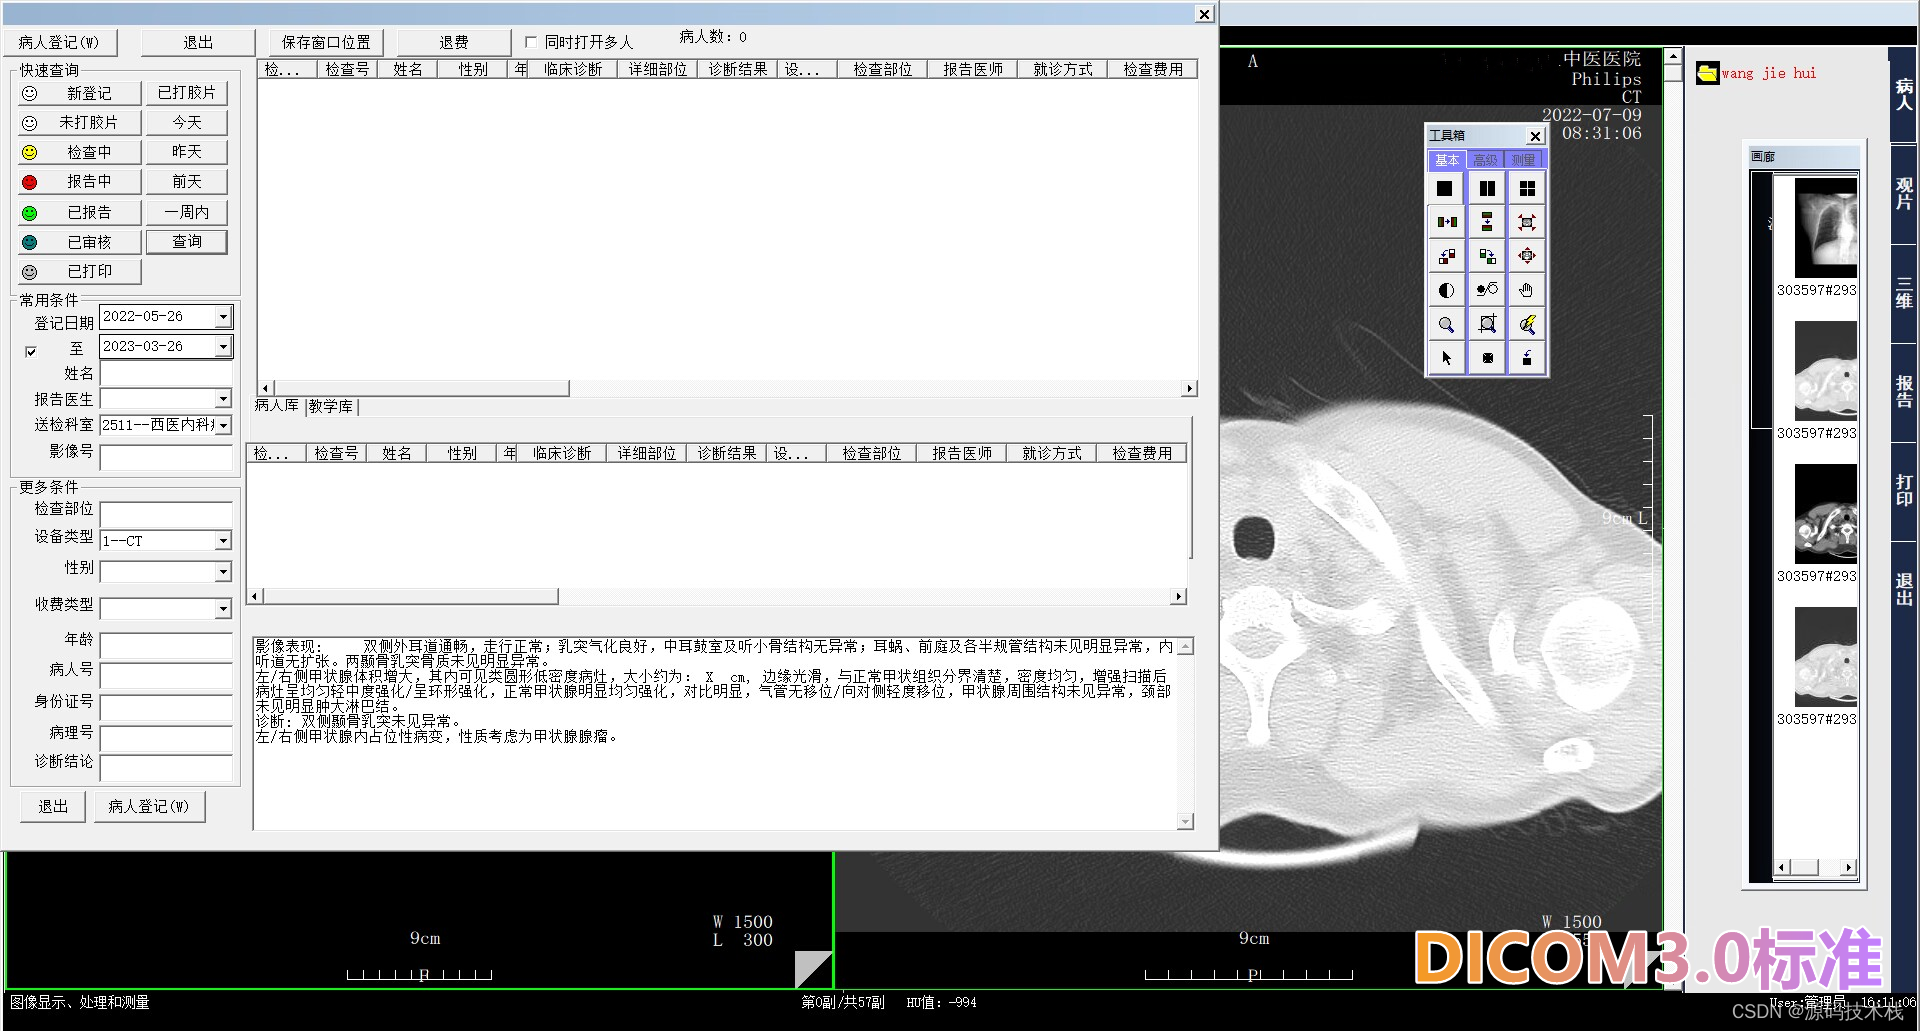

二、系统可实现检查预约、病人信息登记、计算机阅片、影像处理、电子报告书写、胶片打印、数据备份等一系列满足影像科室日常工作的功能。它以灵活的适应性和强大的扩展性为基础,以高效稳定为核心优势,充分结合国内外医学影像技术的发展趋势,遵循DICOM3.0,IHE,HL7等为国际标准开发而成。

1.覆盖登记、分诊、记费、报告生成和分发等内容,与RIS 有机结合;

9.病人报告历史记录管理,可显示同一病人所有检查记录;

11.可根据患者姓名、门诊/住院号、检查设备、检查部位、影像号、检查日期时间等组合查询,方便医生针对多种条件下获得影像资料的工作;